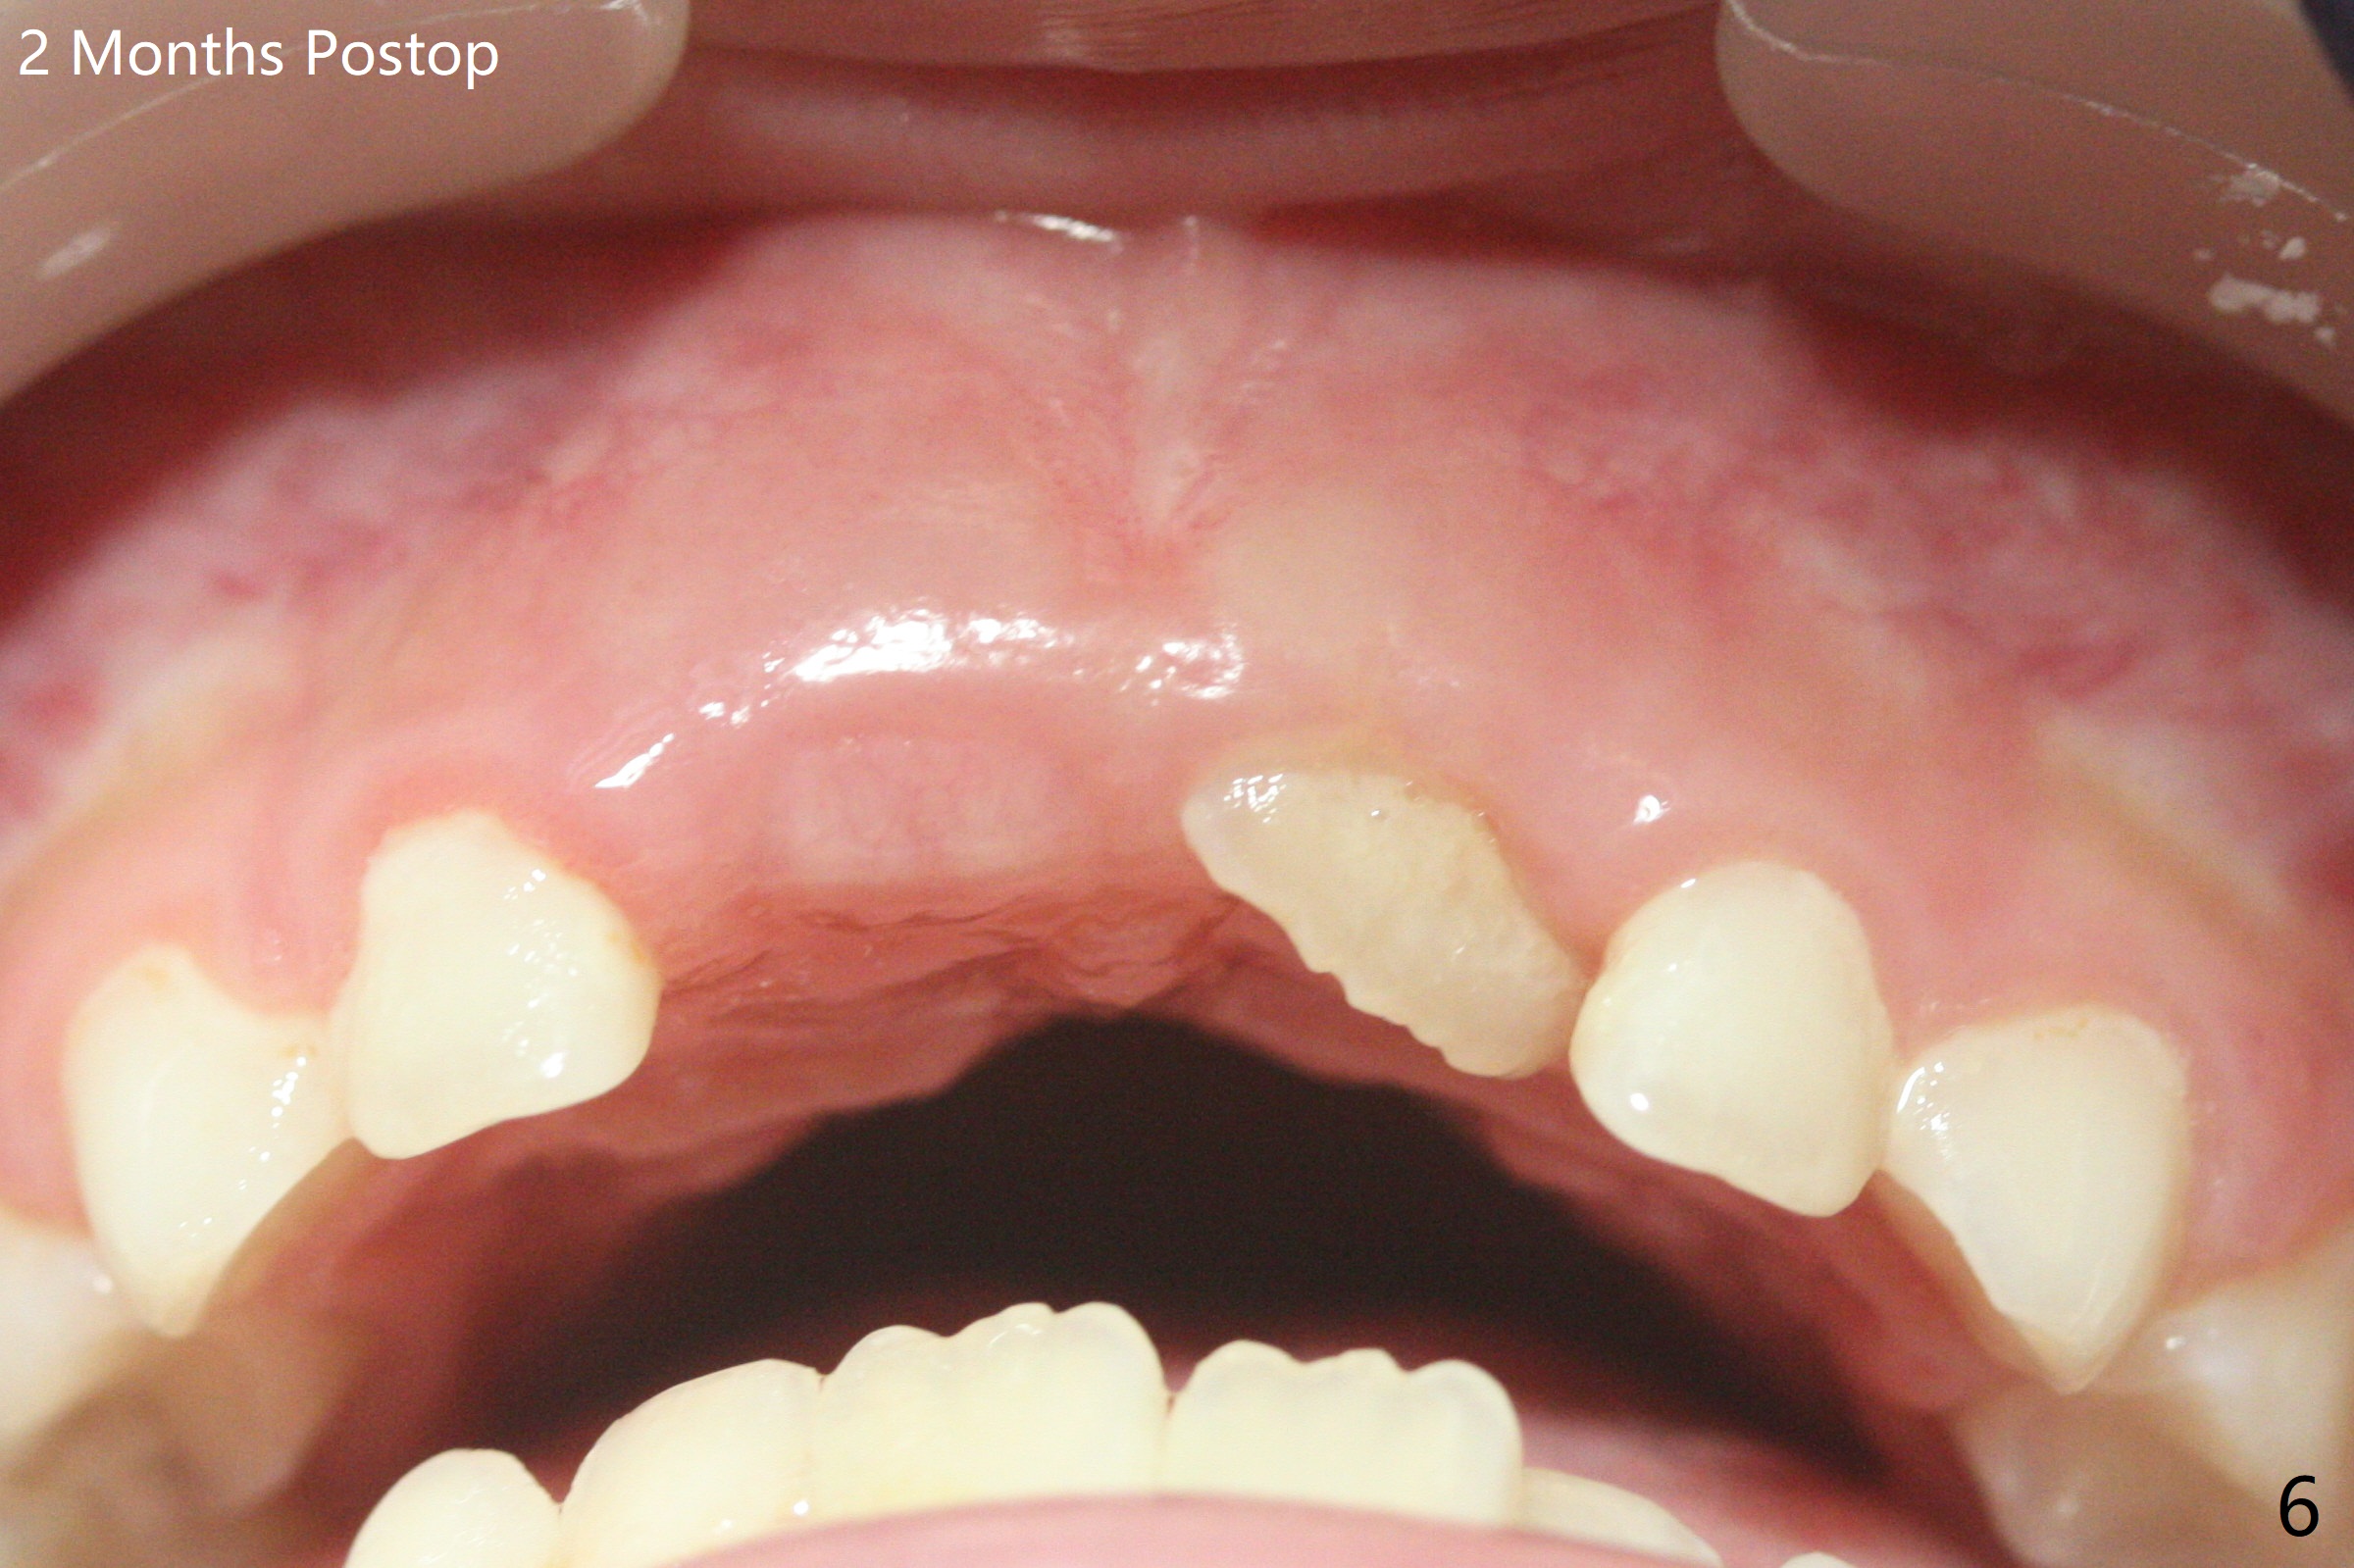

6岁11月女上乳中切牙松动许久,但不脱落,根尖片显示正中多生牙(图一:M),CT显示后者位于腭侧(图二:P)。Take preop photos to show whether the lower lateral incisors have erupted or not. If yes, remove the upperdeciduous central incisors. 一个月后病人回来时,右上乳中切牙已脱落,左上松动 ,术中后者好像影响视野而拔除,腭侧切口,暴露左上1后,拔除多生牙(图三)。 术后3个星期左上中切牙萌出,扭转,反合(图四,五)。术后六个月仍旧如此(图六,七),右上中切牙未萌出,小孩害怕促进萌出手术。准备制作活动矫正器。